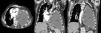

In view of the patient's poor progress after evacuation of pleural fluid and findings suggestive of right heart failure, transthoracic echocardiography was performed, which revealed a hypoechogenic mass in the inferolateral wall of the left ventricle, with dilation of the left atrium, slight pericardial effusion, preserved LVEF, and dilated inferior vena cava without inspiratory collapse. Chest–abdomen computed tomography (CT) was performed, showing a soft tissue mass in the medial portion of the posterior chest wall, measuring 6×3cm, with pericardial infiltration, mass effect, and associated small pericardial effusion. A significant increase in the pleural collection compared to previous studies was visualized, occupying practically the entire hemithorax, causing compressive atelectasis of the lung with contralateral mediastinal shift and cardiac compression (Fig. 1).

Chest CT with contrast medium, axial (left) and coronal slices (center and right): pleural mass in the medial portion of the anterior left chest wall with pericardial infiltration (solid arrows), and a large collection in the left hemithorax, corresponding with chronic pyothorax (dotted arrows), together causing contralateral mediastinal shift and cardiac compression.